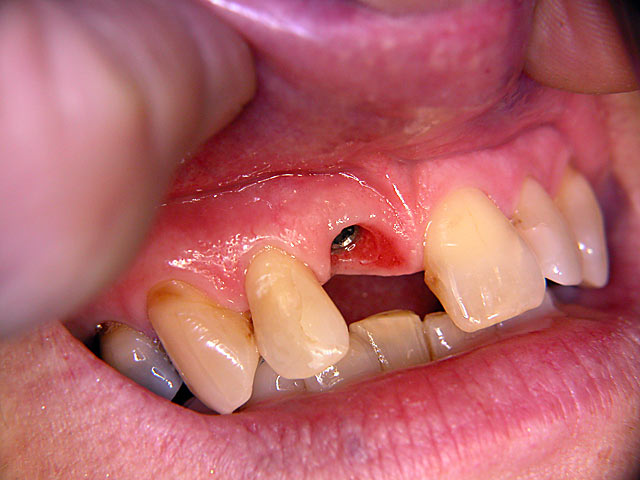

Die folgenden Patientenfälle sollen Ihnen einen Einblick in die Möglichkeiten der modernen Implantation geben.

Frontzahn-Implantation:

Sofort-Implantation: